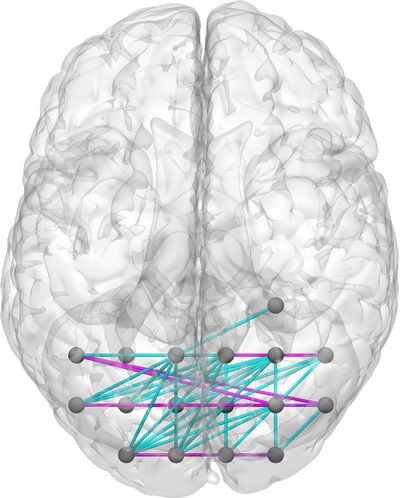

To gain a better understanding of the neighborhood set in the context of our application, let us denote and the pair of -D points in the brain that define the connectome coordinate . Then, the first-order neighborhood set of can be written precisely as 111If or are on the boundary of the brain volume, then neighboring points outside the brain volume are excluded from .

Fig. 2 provides a pictorial illustration of in the case of a -D connectome, where the nodes reside in -D space.

in -D Connectome Space